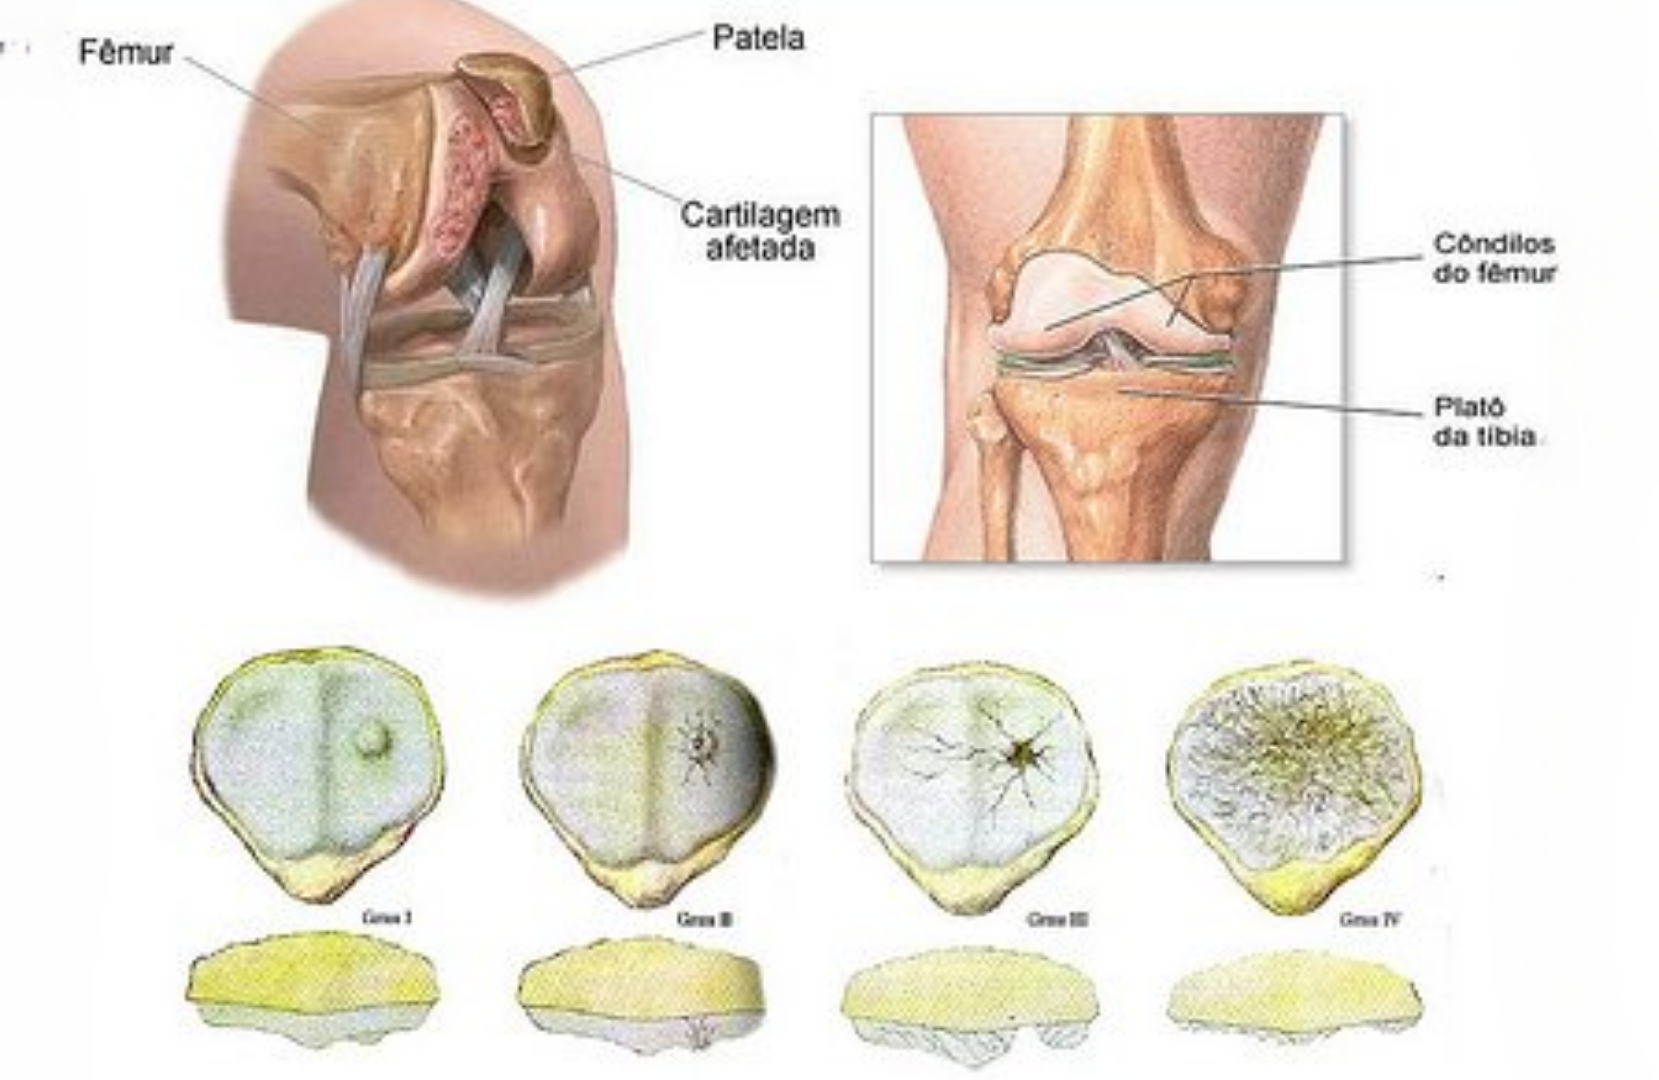

Condromalácia

O desgaste da cartilagem atrás da patela

Conheça os sinais de condromalácia, por que ela afeta tantas pessoas ativas e o que realmente funciona no tratamento (além do fortalecimento muscular).